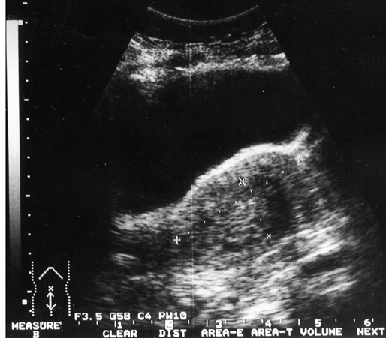

Клинико-морфологические и ультразвуковые параллели позволяют клиницисту на дооперационном периоде составить представление о степени распространения опухолевого процесса, наличия метастазов не только в зонах регионарного метастазирования, но и в органах брюшной полости (рис. 1–4).

Рисунок 4. Тотальное поражение полости матки с переходом на цервикальный канал

Полученная информация дает возможность хирургу планировать тактику ведения больных РТМ, включая главный этап — объем хирургического вмешательства. Это касается выполнения экстирпации матки с придатками и удаления лимфатических узлов у больных с опухолевым поражением всей полости матки и метастазами в лимфатические узлы, расширенной пангистерэктомии при распространении опухоли на цервикальный канал и экстирпации матки с придатками, резекции большого сальника — при метастатическом поражении придатков матки или серозно-папиллярном раке эндометрия.

Совпадение морфологических и сонографических данных о размерах первичной опухоли в матке и ее локализации отмечено соответственно в 86 и 45,7% наблюдений. Значительна частота совпадений и при большом поражении полости матки. Так, у 52,4% пациенток с тотальным поражением полости матки и у 88,2% пациенток с локализацией опухоли в полости матки с переходом на цервикальный канал данные УЗТ и гистологического заключения совпали. Этот показатель снижается до 15,8% при локализации аденокарциномы в области дна матки и ее трубных углов.

Практически у половины больных с метастазами рака эндометрия в лимфатические узлы показатели УЗИ совпали с данными морфологии.